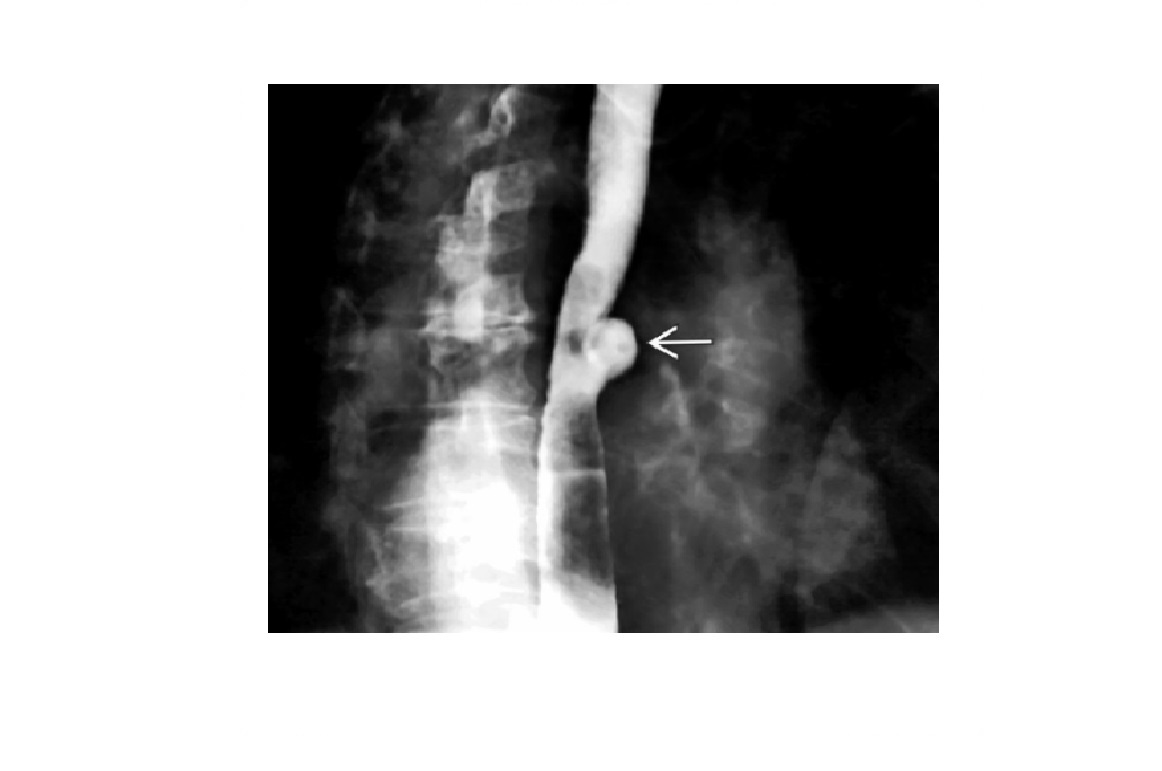

Epiphrenic diverticulum

Large saccular outpouching just above the diaphragm, right side

Can be mistaken for paraesophageal hernia - usually in on the left

associated with dysmotility disorders